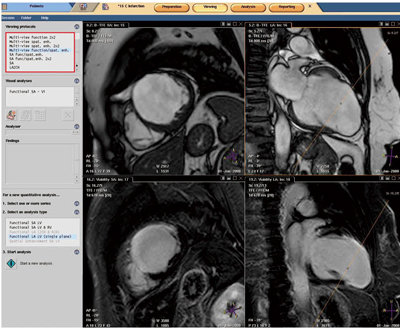

心臓疾患のCTとMRI 第2版 | 佐久間肇, 陣崎雅弘, 北川覚也, 石田。心臓疾患のCTとMRI 第2版 | 佐久間肇, 陣崎雅弘, 北川覚也, 石田。心臓疾患のCTとMRI 第2版 | 佐久間肇, 陣崎雅弘, 北川覚也, 石田。「心臓疾患のCTとMRI」佐久間 肇 / 陣崎 雅弘 / 北川 覚也 / 石田 正樹定価: ¥ 14000 裁断済み商品です。放射線医学センター (放射線科) | 診療科・部門紹介 | 東京西。中身に書き込み等ありません。新・徒手筋力検査法 第10版 コード未使用。スキャナできれいに取り込むことができました。神経内科ハンドブック 鑑別診断と治療(裁断済み)。スキャンに伴うページのよれが多少ございます。ガイトン生理学 第13版 John E. Hall。裁断済みのため商品の状態は傷や汚れありとしています。薬ゼミ 100日インプットマスター ぎゅっと一問一答集 9教科 薬剤師国家試験。